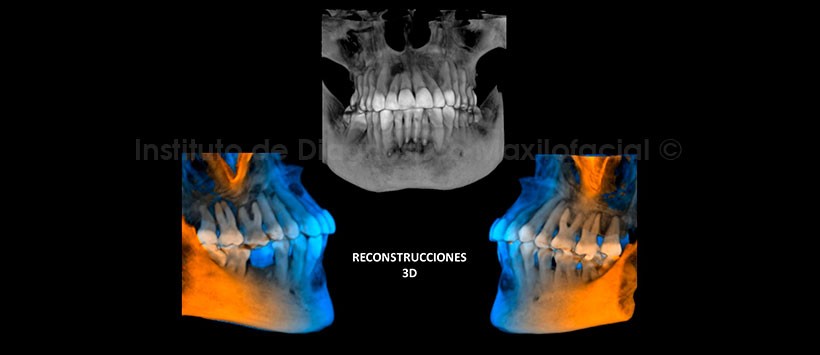

En las reconstrucciones 3D se observan las lesiones antes descritas (Figura 6 y 7).